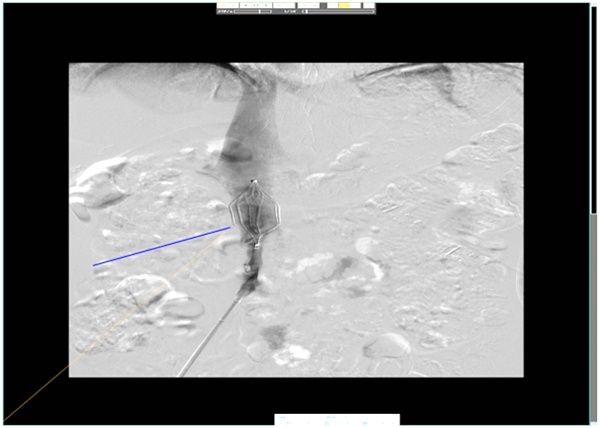

为患者实施局麻后,穿刺右股静脉,置入8F血管鞘,沿鞘送入8FPIG造影导管行下腔静脉造影,导管、导丝配合,确定双肾肾静脉位置,于开口位置放置静脉滤器一枚。